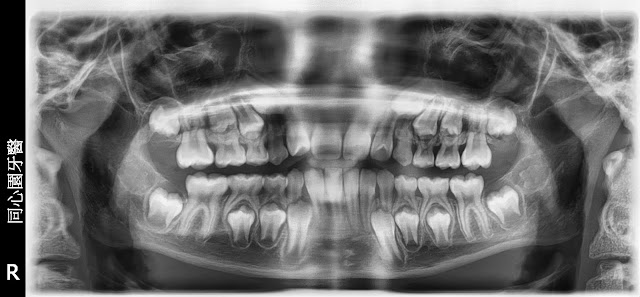

5歲(男)